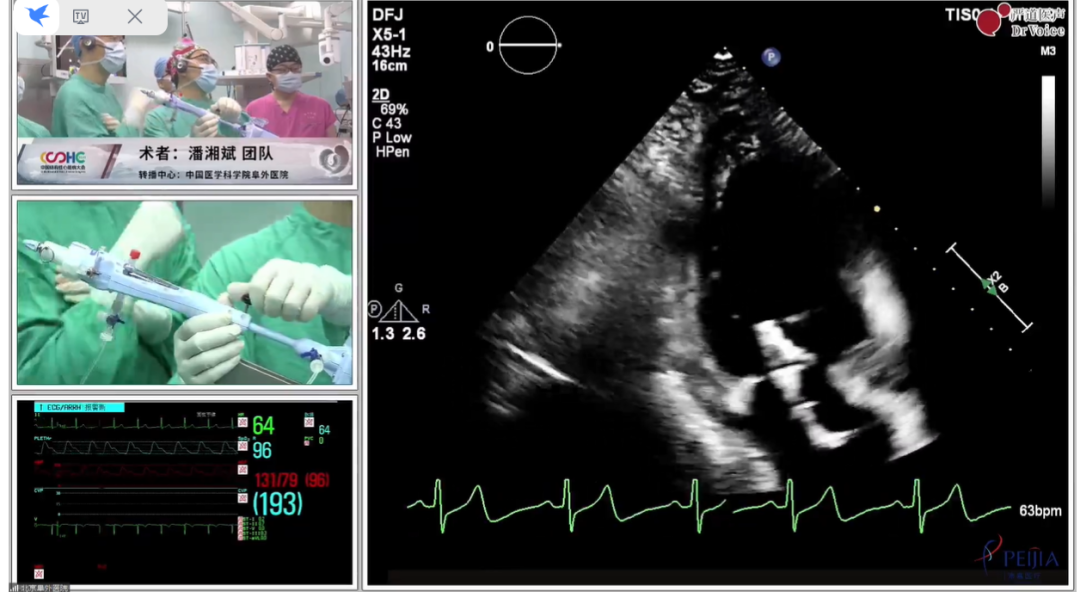

将MitraClip™推进左心室并向后拉,直到二尖瓣瓣叶被抓捕,关闭夹子,反流几乎消失

释放MitraClip™,超声显示反流降至微量,平均跨瓣压差3mmHg, 患者各项生理指标正常,手术顺利完成

术后即刻超声图